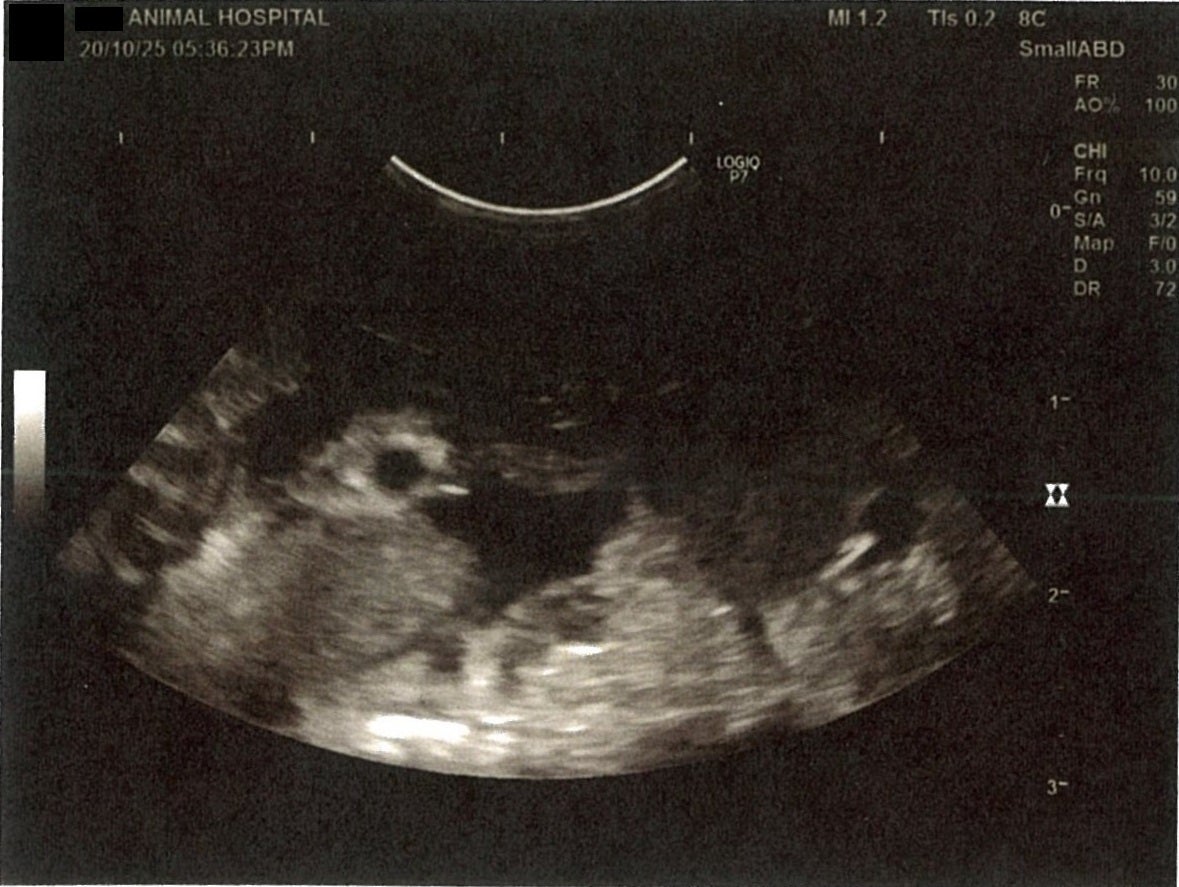

《心臓周りの胸部以外の全ての腹部で腹水がみられるとの診断です》

大網という部分で内臓を包む膜のようなものです。その周りに腹水が溜まっています。

膀胱周りに腹水が確認できるエコー写真